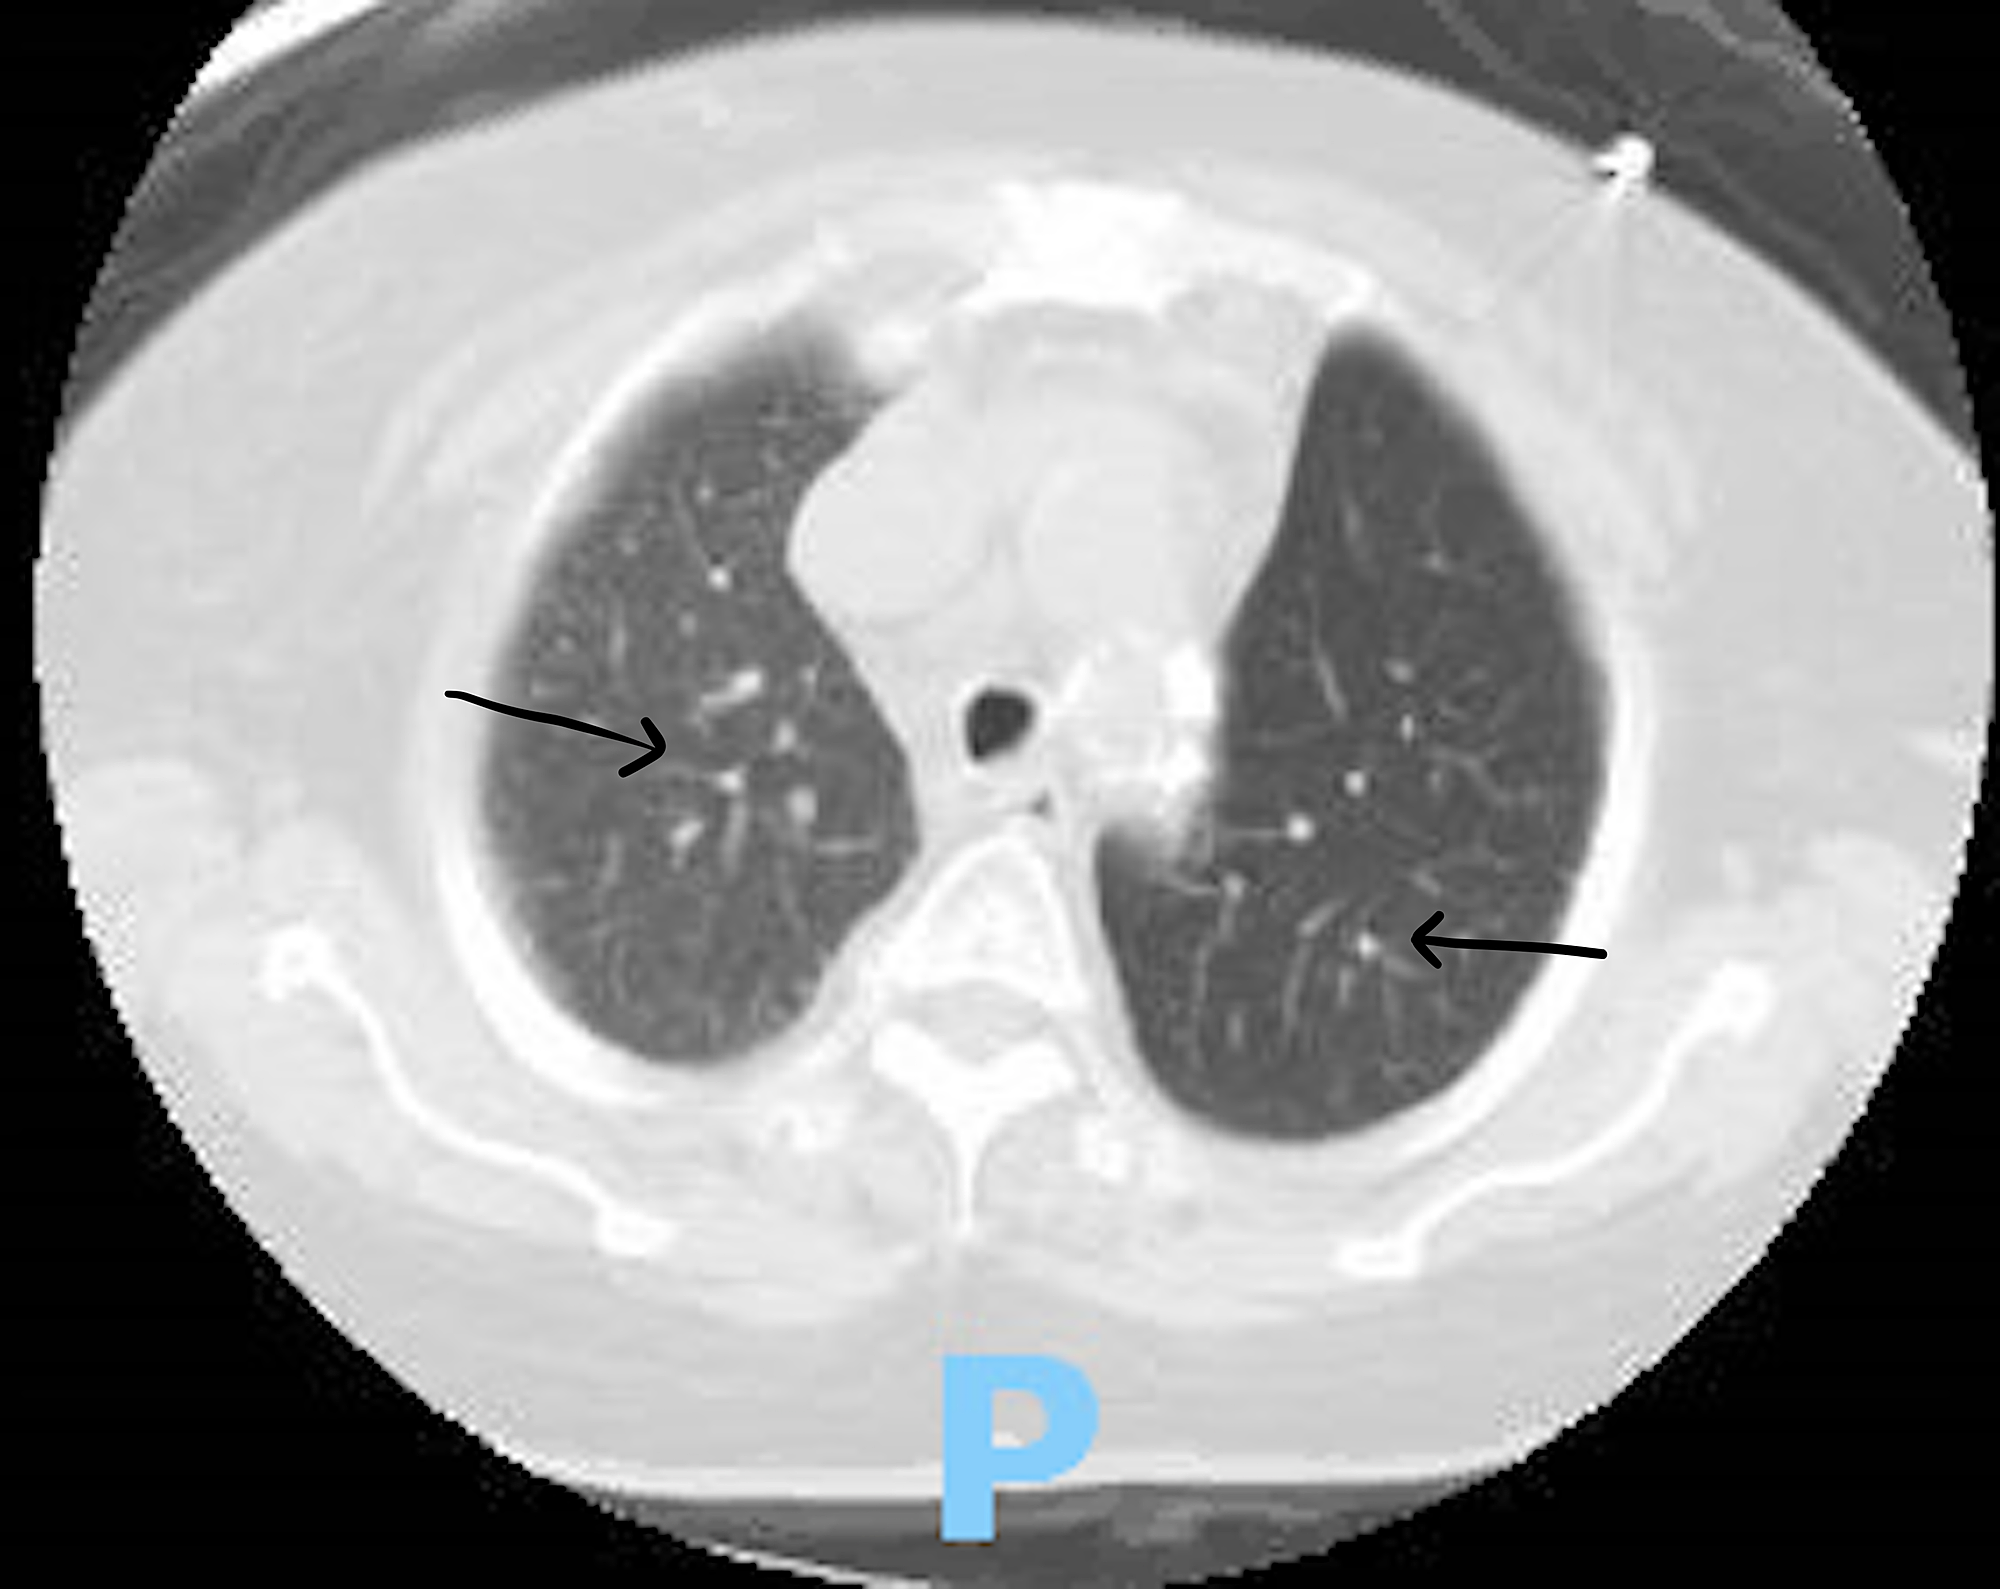

From err.ersjournals.com

Multiple pulmonary nodules in a male with psoriatic arthritis European Respiratory Society Arthritis Symptoms Lungs Ra can cause several types of lung problems, such as interstitial lung disease, airway obstruction, lung nodules and pleural disease. But by the time these signs appear, irreversible lung damage has often already. Learn how rheumatoid arthritis (ra) can affect the lungs and cause interstitial lung disease (ild), a serious and potentially fatal condition. Learn about the types and complications. Arthritis Symptoms Lungs.